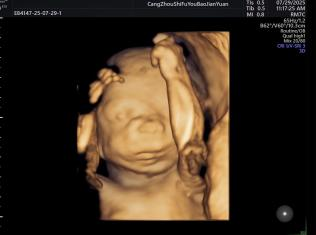

给宝宝的“立体影像”,让产检更安心

科室采用三维/四维超声技术开展胎儿检查,能清晰呈现胎儿面部及身体关键结构的影像,让准父母直观感受宝宝的发育状态。检查中,医生会借助技术对唇腭裂、小下颌等结构异常进行细致观察,同时基于三维容积数据,从多个平面评估胎儿心脏、大脑、脊柱等重要部位,为孕期健康管理提供专业参考。

正常胎儿面部三维照片